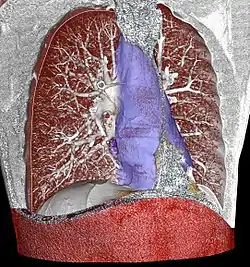

3D rendering of a high resolution computed tomography of the thorax, with mediastinum marked in blue.